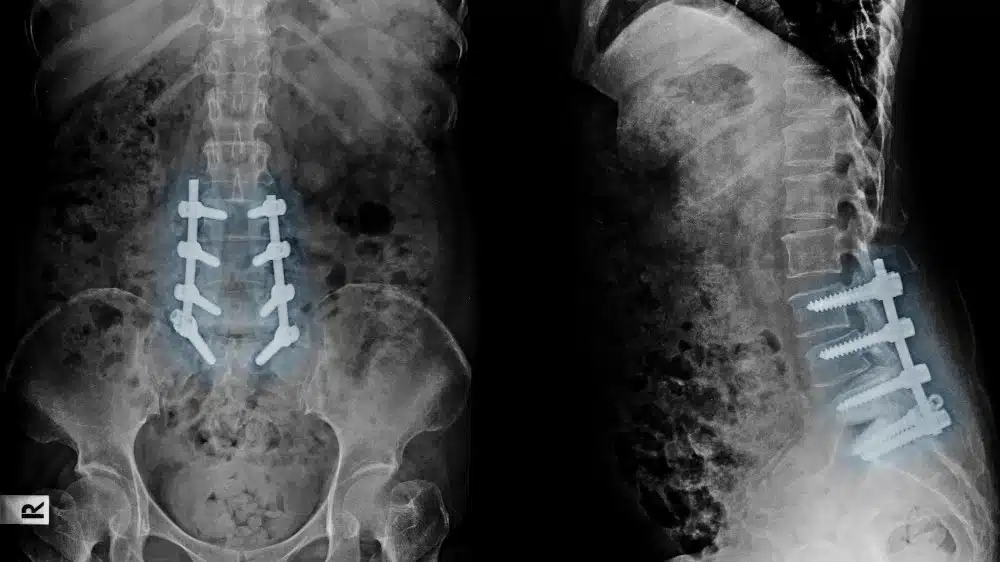

Gesundheits-Statistik belegt: Rücken-Operation oft unnötig

Bei Rückenbeschwerden wird in Deutschland zu schnell zum Messer gegriffen

Zu viele Patienten mit unspezifischen Rückenschmerzen im Krankenhaus

Bei Rückenschmerzen kommt es immer wieder zu Fehlversorgungen. Ambulante Maßnahmen und Übungen sind oft besser geeignet.